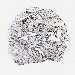

BRCA TCGA BRCA VALIDATION PROTEIN EXPRESSION